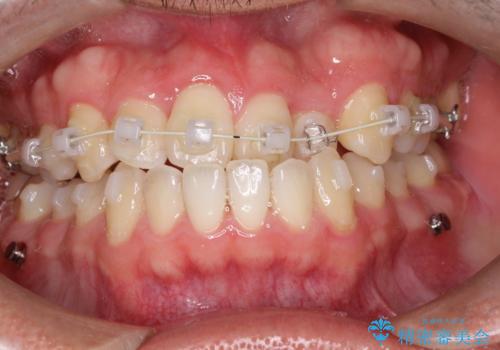

前歯が反対にかんでいる インビザラインとワイヤーを組み合わせた矯正治療

- 前歯が正常とは反対にかんでいるとのことで、来院されました。

患者様がマウスピースを希望されていましたが、上の前歯のがたつきを先にワイヤーで改善する方が早く治療が終了することが可能であるとお伝えし、上顎のみ半年間ワイヤーで治療を行いました。

マウスピースのみでの治療も可能でしたが、治療期間がもう少し延長していた可能性があります。